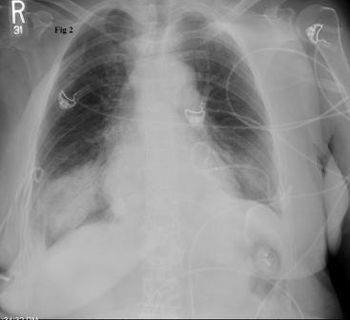

Worsening respiratory symptoms and fatigue of 6 months’ duration brought a 44-year-old woman in for evaluation. Diagnosed with asthma 2 years earlier, she was compliant with, but unresponsive to treatment. Your impressions?